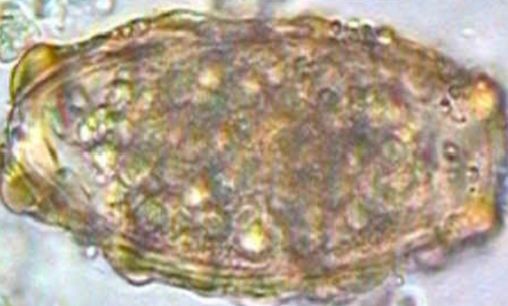

Ascaris lumbricoides unfertilized

Ascaris lumbricoides fertilized